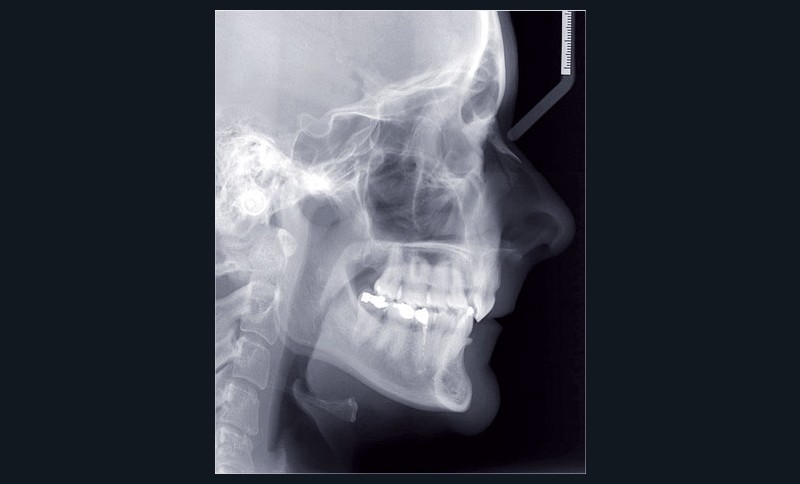

Cas n° 2

Nous lui avons donc proposé un traitement d’alignement avec maintien des 14 et 24 en position de 13 et 23 et optimisation du torque pour favoriser un développement des arcades et chercher à améliorer le sourire et le soutien labial.

Un appareillage Damon métal a été mis en place, réalisé à partir d’un set up numérique Insignia pour obtenir un contrôle précis des torques et de la forme d’arcade et réduire le temps de finition grâce à un collage indirect très précis.

L’objectif, en utilisant la technique Insignia est de réduire le temps de traitement de 28 à 18 mois avec 12 rendez-vous (fig. 5 à 14).